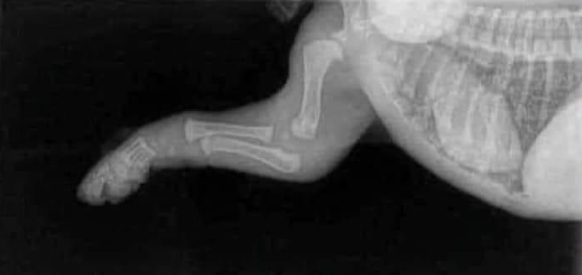

LE SQUELETTE DE VOTRE CHIOT

Votre chiot Berger Allemand a 2 mois, il va grandir jusqu'à 15 mois. Il faut avoir en tête ces photos de radios, afin de comprendre, qu'il est important de prendre soin de lui, de sa croissance jusqu'à la fin de la formation de son squelette.

Radio patte arrière Radio pattes avant

Nous avons spécialement choisi des reproducteurs indemnes de dysplasie sur plusieurs générations, ils sont nourris, avec des croquettes protéinées, et complémentés en viande rouge et ou viande crue, poulet cuit, sardines. On s'attache beaucoup à leur santé, leur apport en bons nutriments. On fait donc tout pour que votre chiot soit issu de géniteurs en bonne santé.